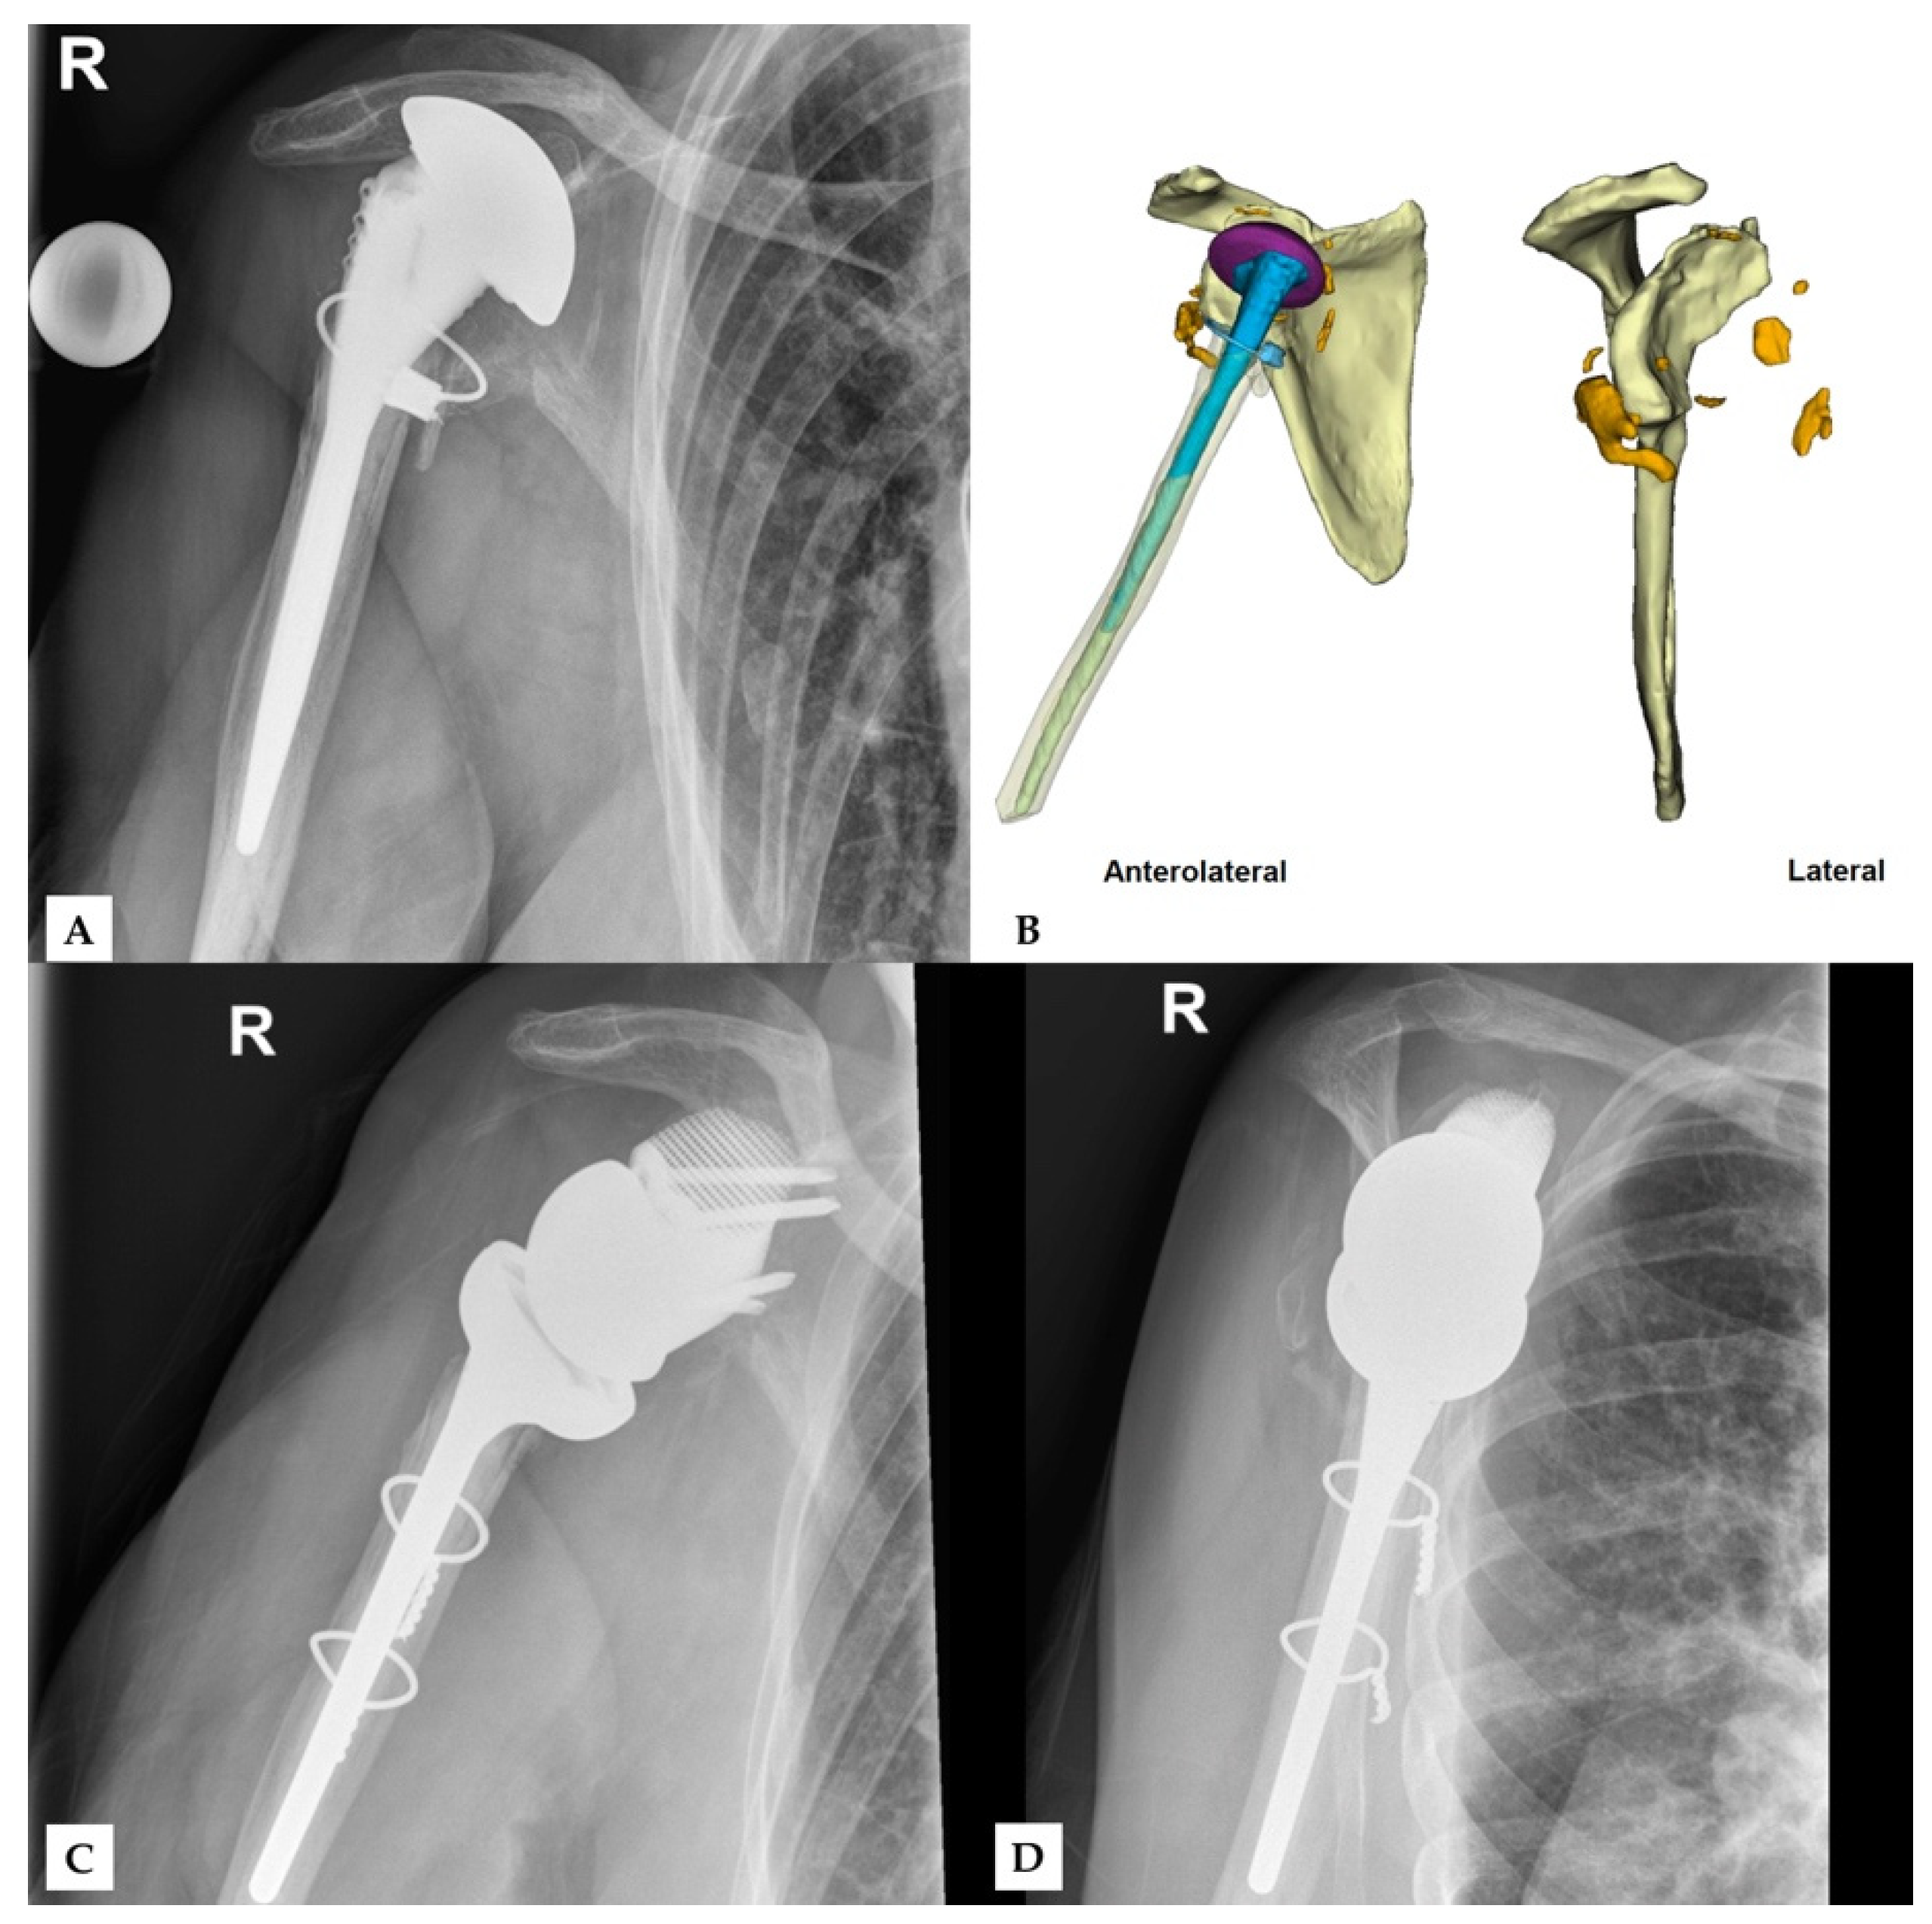

Figure 1, Figure 2 and Figure 3 show an example procedure on a case with severe bone loss due to glenoid loosening after primary anatomical TSA. Septic loosening must be excluded using a two-time procedure with sonication and tissue sampling. Radiographs in the anteroposterior and axial directions and an additional CT scan are necessary before surgery. The CT scan must be performed according to the manufacturer’s specifications to assess the bone stock and plan an adequate prosthesis. The original glenoid is reconstructed using statistical shape modelling, and an appropriate centre of rotation is proposed [8]. The position of the screws is proposed depending on the best direction and maximum possible length of the intraosseous screw length according to bone stock and quality.

Figure 1. One case of revision reverse total shoulder arthroplasty severely damaged glenoid in the setting of implant loosening after anatomical TSA. Preoperative X-rays were performed in the (A) anteroposterior and (B) axial directions. (C) The surgical procedure consisted of two-time revision with explantation of the anatomical prosthesis and exclusion of infection via sonication and tissue samples. (D) Surgery using a custom-made glenoid component was performed after confirmation of aseptic loosening.

Figure 4. Second case of revision rTSA. The preoperative X-ray (A) after removal of the prior implant shows extensive damage of the glenoid and the proximal humerus. Bone fragments (orange) and excess cement (grey) can be seen in the CT-scan (B), while the preoperative model (C) shows the scapula after the removal of these fragments. The final outcome shows the glenoid implant in the correct position (D). Reprinted with permission from Materialise. ©2021 Materialise NV.